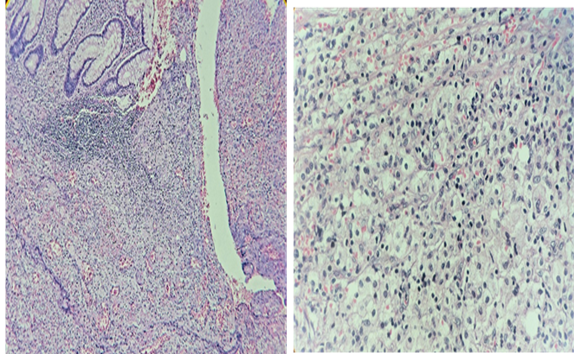

Se sometió a laparotomía exploradora y en pared abdominal se encontró 500ml de material purulento fétido en sitio de tumoración, en cavidad abdominal asas intestinales adheridas a ciego donde se encontró plastrón y apéndice cecal inflamada en su tercio distal con perforación en tercio medio. La biometría hemática a las 72 horas reportó disminución de leucocitos, el resultado del cultivo de exudado de pared abdominal fue positivo a Streptococcus viridans sensible a imipinem y clindamicina (Tabla 2), el diagnóstico histopatológico fue de apendicitis xantogranulomatosa (Figura 3). La evolución fue estable, con mejoría y en ocho días egresó a domicilio sin ninguna complicación aparente.

Figura 3 Reporte histopatológico: Diagnóstico de Apendicitis xantogranulomatosa de acuerdo con las características celulares encontradas y descritas a continuación. A) Mucosa apendicular con abundante infiltrado inflamatorio crónico y agudo con trayecto transmural bordeado por tejido de granulación e inflamatorio donde se aprecian abundantes histiocitos espumosos en la muscular propia y subserosos (Hematoxilina-eosina, 10X). B) Histiocitos con citoplasma espumoso abundante (Hematoxilina-eosina, 40X)

La IXG es un proceso inflamatorio crónico que lleva a la destrucción local de los tejidos propios del órgano afectado o de los localizados en la vecindad de este. Este tipo de inflamación se ha descrito en riñón, vesícula biliar, próstata, epidídimo, ovario y rara vez en el apéndice cecal. Histológicamente posee macrófagos en los cuales se depositan lípidos con linfocitos que le confiere un aspecto “espumoso”, células plasmáticas, neutrófilos y células.